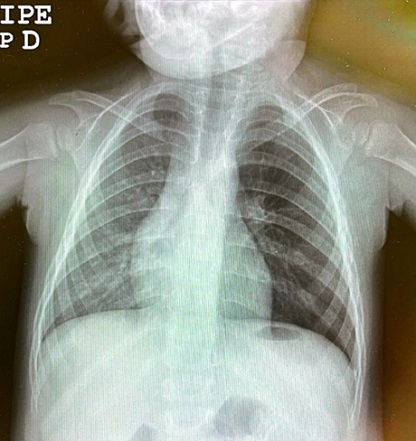

Niña de 2 años valorada en consulta por tos seca nocturna y escucha de sibilancias de una semana de evolución, sin fiebre asociada. Diagnóstico inicial de broncoespasmo en medio hospitalario, tratado con broncodilatadores inhalados. Ante la falta de mejoría se revisa en el centro de salud y se aprecia en la auscultación asimetría con hipoventilación del campo pulmonar izquierdo, por lo que se deriva a urgencias, donde la radiografía se informa como: “asimetría entre ambos campos pulmonares con aumento de la radiolucencia y del volumen del pulmón izquierdo compatible con atrapamiento aéreo” (Figura 1). Ante la sospecha de cuerpo extraño bronquial, se programa un TAC, que informa la presencia de una lesión endobronquial dependiente de la pared posterior del tercio medio del bronquio principal izquierdo (Figura 2). El TAC describe una lesión redondeada y de aspecto polipoide con obstrucción prácticamente completa de la luz bronquial. Se realiza broncoscopia con toma de biopsias y resultado anatomopatológico compatible con granuloma, por lo que se programa exéresis de la lesión vía endoscópica. El estudio anatomopatológico confirma inflamación crónica granulomatosa necrotizante. Baciloscopia y cultivo de micobacterias de lavado broncoalveolar: Mycobacterium avium. Ante este resultado, se inició un tratamiento combinado con rifampicina, etambutol y azitromicina, sin toxicidad y con buena adherencia. A nivel clínico, tras la resección hay una mejoría clínica respiratoria sin complicaciones hasta los cinco meses, cuando, por la objetivación de cianosis de esfuerzo por los padres, se solicita radiografía en la que se aprecia un inicio de consolidación en lóbulo inferior izquierdo, prescribiendo tratamiento antibiótico con amoxicilina-clavulánico. Se programaron broncoscopia y TAC que descartaron recidiva. Se recogieron muestras para un cultivo convencional y micobacterias, siendo negativas. Se solicitó a su vez panel de virus respiratorios, con resultado positivo en rhinovirus y enterovirus.